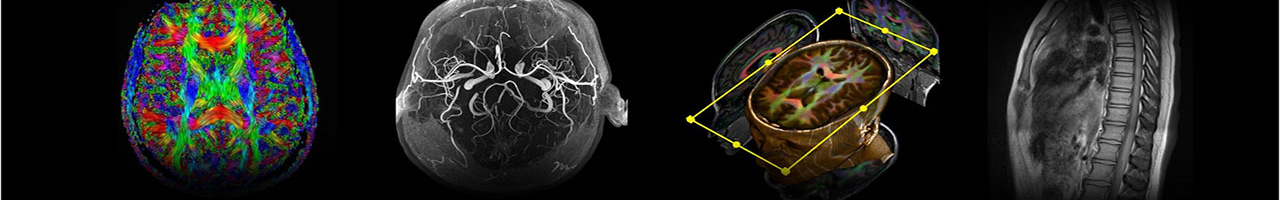

The Research MRI Core provides resources at UAB for state-of-the-art magnetic resonance imaging experiments and analyses for examining brain and body anatomy and function both in health and disease.

Research ranges from basic MRI engineering and physics to multisite clinical trials. We support investigators with advanced imaging of the whole body, including the brain, spinal cord, eye, liver, skeletal muscle, heart, and kidney.